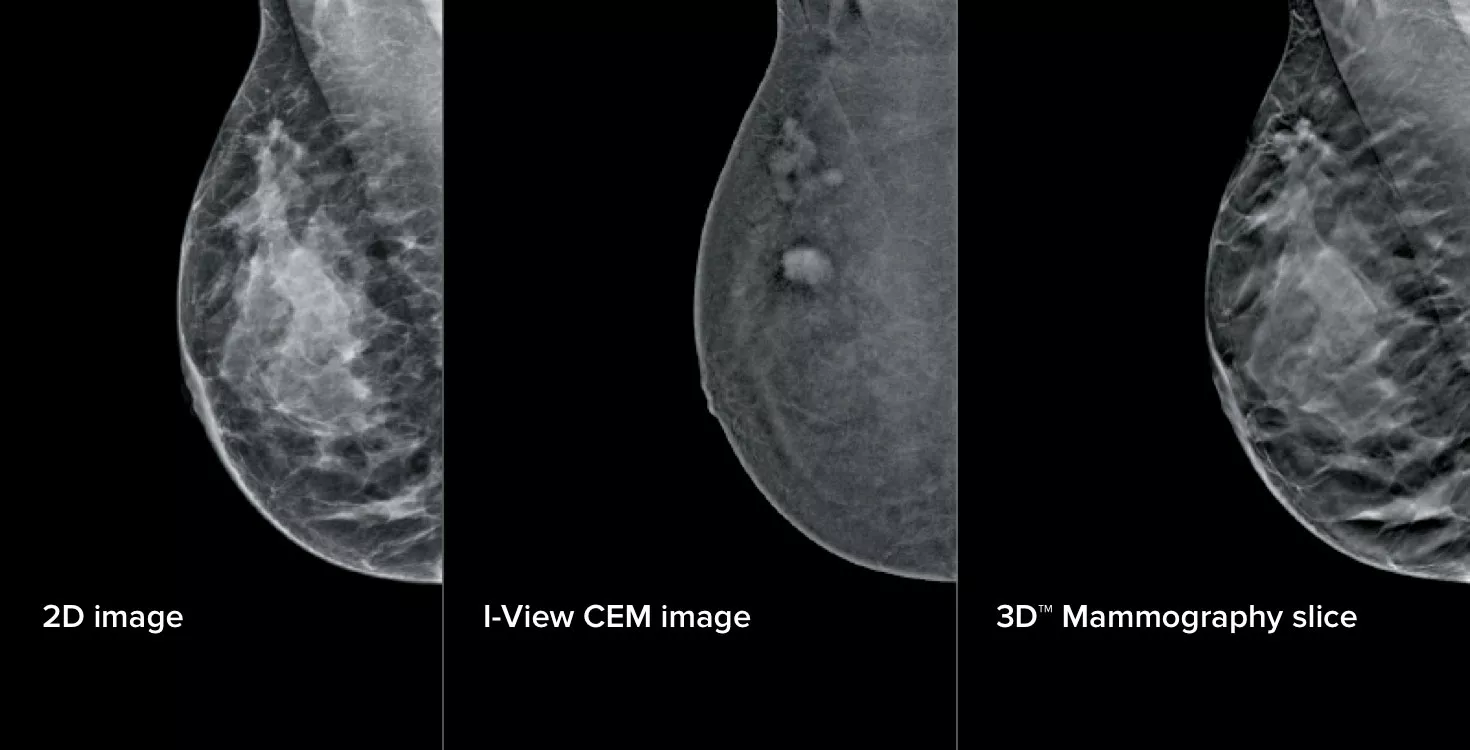

Die kontrastverstärkte Mammografie (CEM), d. h. eine Brust-Untersuchung unter Verwendung von jodiertem Kontrastmittel zur Erkennung von Bereichen mit erhöhter Blutzufuhr, kann die Bildgebung einer verdächtigen Läsion unterstützen. Die I-View Software erfasst sowohl anatomische als auch funktionelle Daten in einer einzigen Untersuchung mit CEM-, 2D- und Tomosynthesebildern aus einer einzigen Kompression.1

Diese Software erfasst sowohl anatomische als auch funktionelle Daten in einer einzigen Untersuchung dank unserer 2D-, Kontrast- und Tomosynthese-Bilder aus einer einzigen Kompression.1